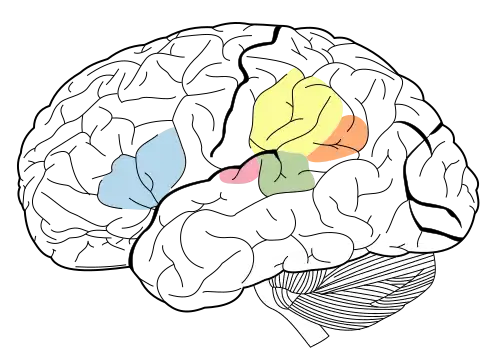

A study conducted by Price and colleagues evaluated the regions involved in auditory word perception and repetition. This is an example of how results and methods need to be read carefully as results can be interpreted in many ways. Activations of the left inferior frontal region (otherwise known as Broca's area, see Figure 5 for the location Broca's area and other important language centers) during auditory word processing were found during phonological judgement to auditory stimuli, word retrieval, and semantic judgements [5][15][17]. These tasks all require the with holding of auditory stimuli in auditory-verbal short-term memory while making semantic or phonological judgements. We know that these short-term memory tasks with auditory stimuli increase the activation of Broca's area based on research from Paulesu and colleagues [18] and therefore the role of Broca's area in these tasks may be as a result of phonological rehearsal [13]. Whereas, Fiez et al. interprets the activation in the frontal operculum as phonological analysis, not required for listening to or identifying auditory stimuli [14]. Remember back to the discussion on the ventral stream semantic processing, Binder and colleagues hypothesized similar frontal activation as a result of "language executive" functions [11]. Thus, this frontal activation site has been interpreted in different ways, and requires additional research before a solid take on it's role in either the ventral or dorsal stream, or both, is reached.